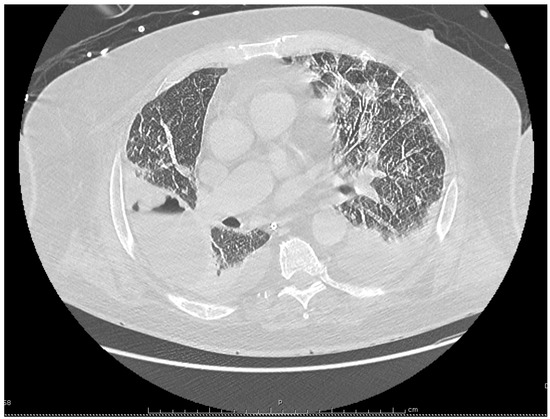

Despite these treatments the patient’s condition deteriorated with the onset of respiratory failure and septic shock, requiring the use of vasoactive drugs and mechanical ventilation. Antimicrobial coverage was therefore broadened with the replacement of cefotaxime and levofloxacin by i.v. meropenem, 2 g every 8 h, and i.v. linezolid 600 mg twice a day, although no pathogenic bacteria had been identified yet. A chest computed tomography (CT) showed bilateral pleural effusions, patchy alveolar infiltrates, and a large abscess in the right lobe measuring 85 by 57 by 53 mm (Figure 2). Intravenous voriconazole 400 mg every 12 h, was thus substituted for fluconazole with concern for an Aspergillus infection, and acyclovir was discontinued.

Figure 2. Chest computed tomography performed on the 21st day of hospitalization, showing bilateral pleural effusions, and the occurrence of a large abscess in the right lung.